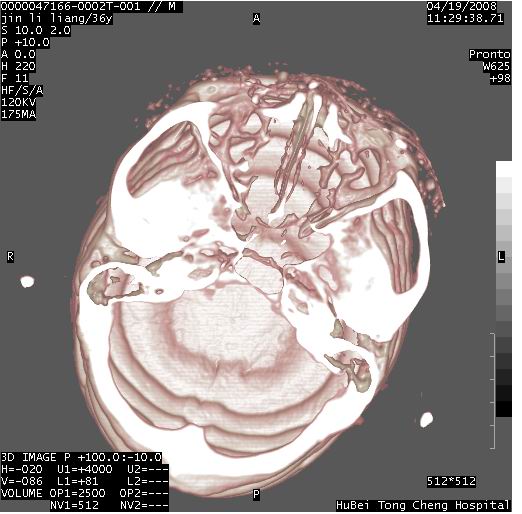

患者 男,36岁。头面部“土炮”炸伤。pe:面目全非,伤口流血不止。

临床诊断:头面部外伤。

颅脑ct轴位平扫(层厚、层距均为10mm),图像如下:

左眼球破裂并异物,眶周、额顶部头皮及软组织挫伤并异物

迎面一炮,满脸开曝。额顶部头皮及软组织挫伤并异物,左眼球破裂积气并异物,典型的面目全非,惨不忍睹。

1左侧眼球破裂并积气,球内、框内异物。

2额部顶部软组织伤。